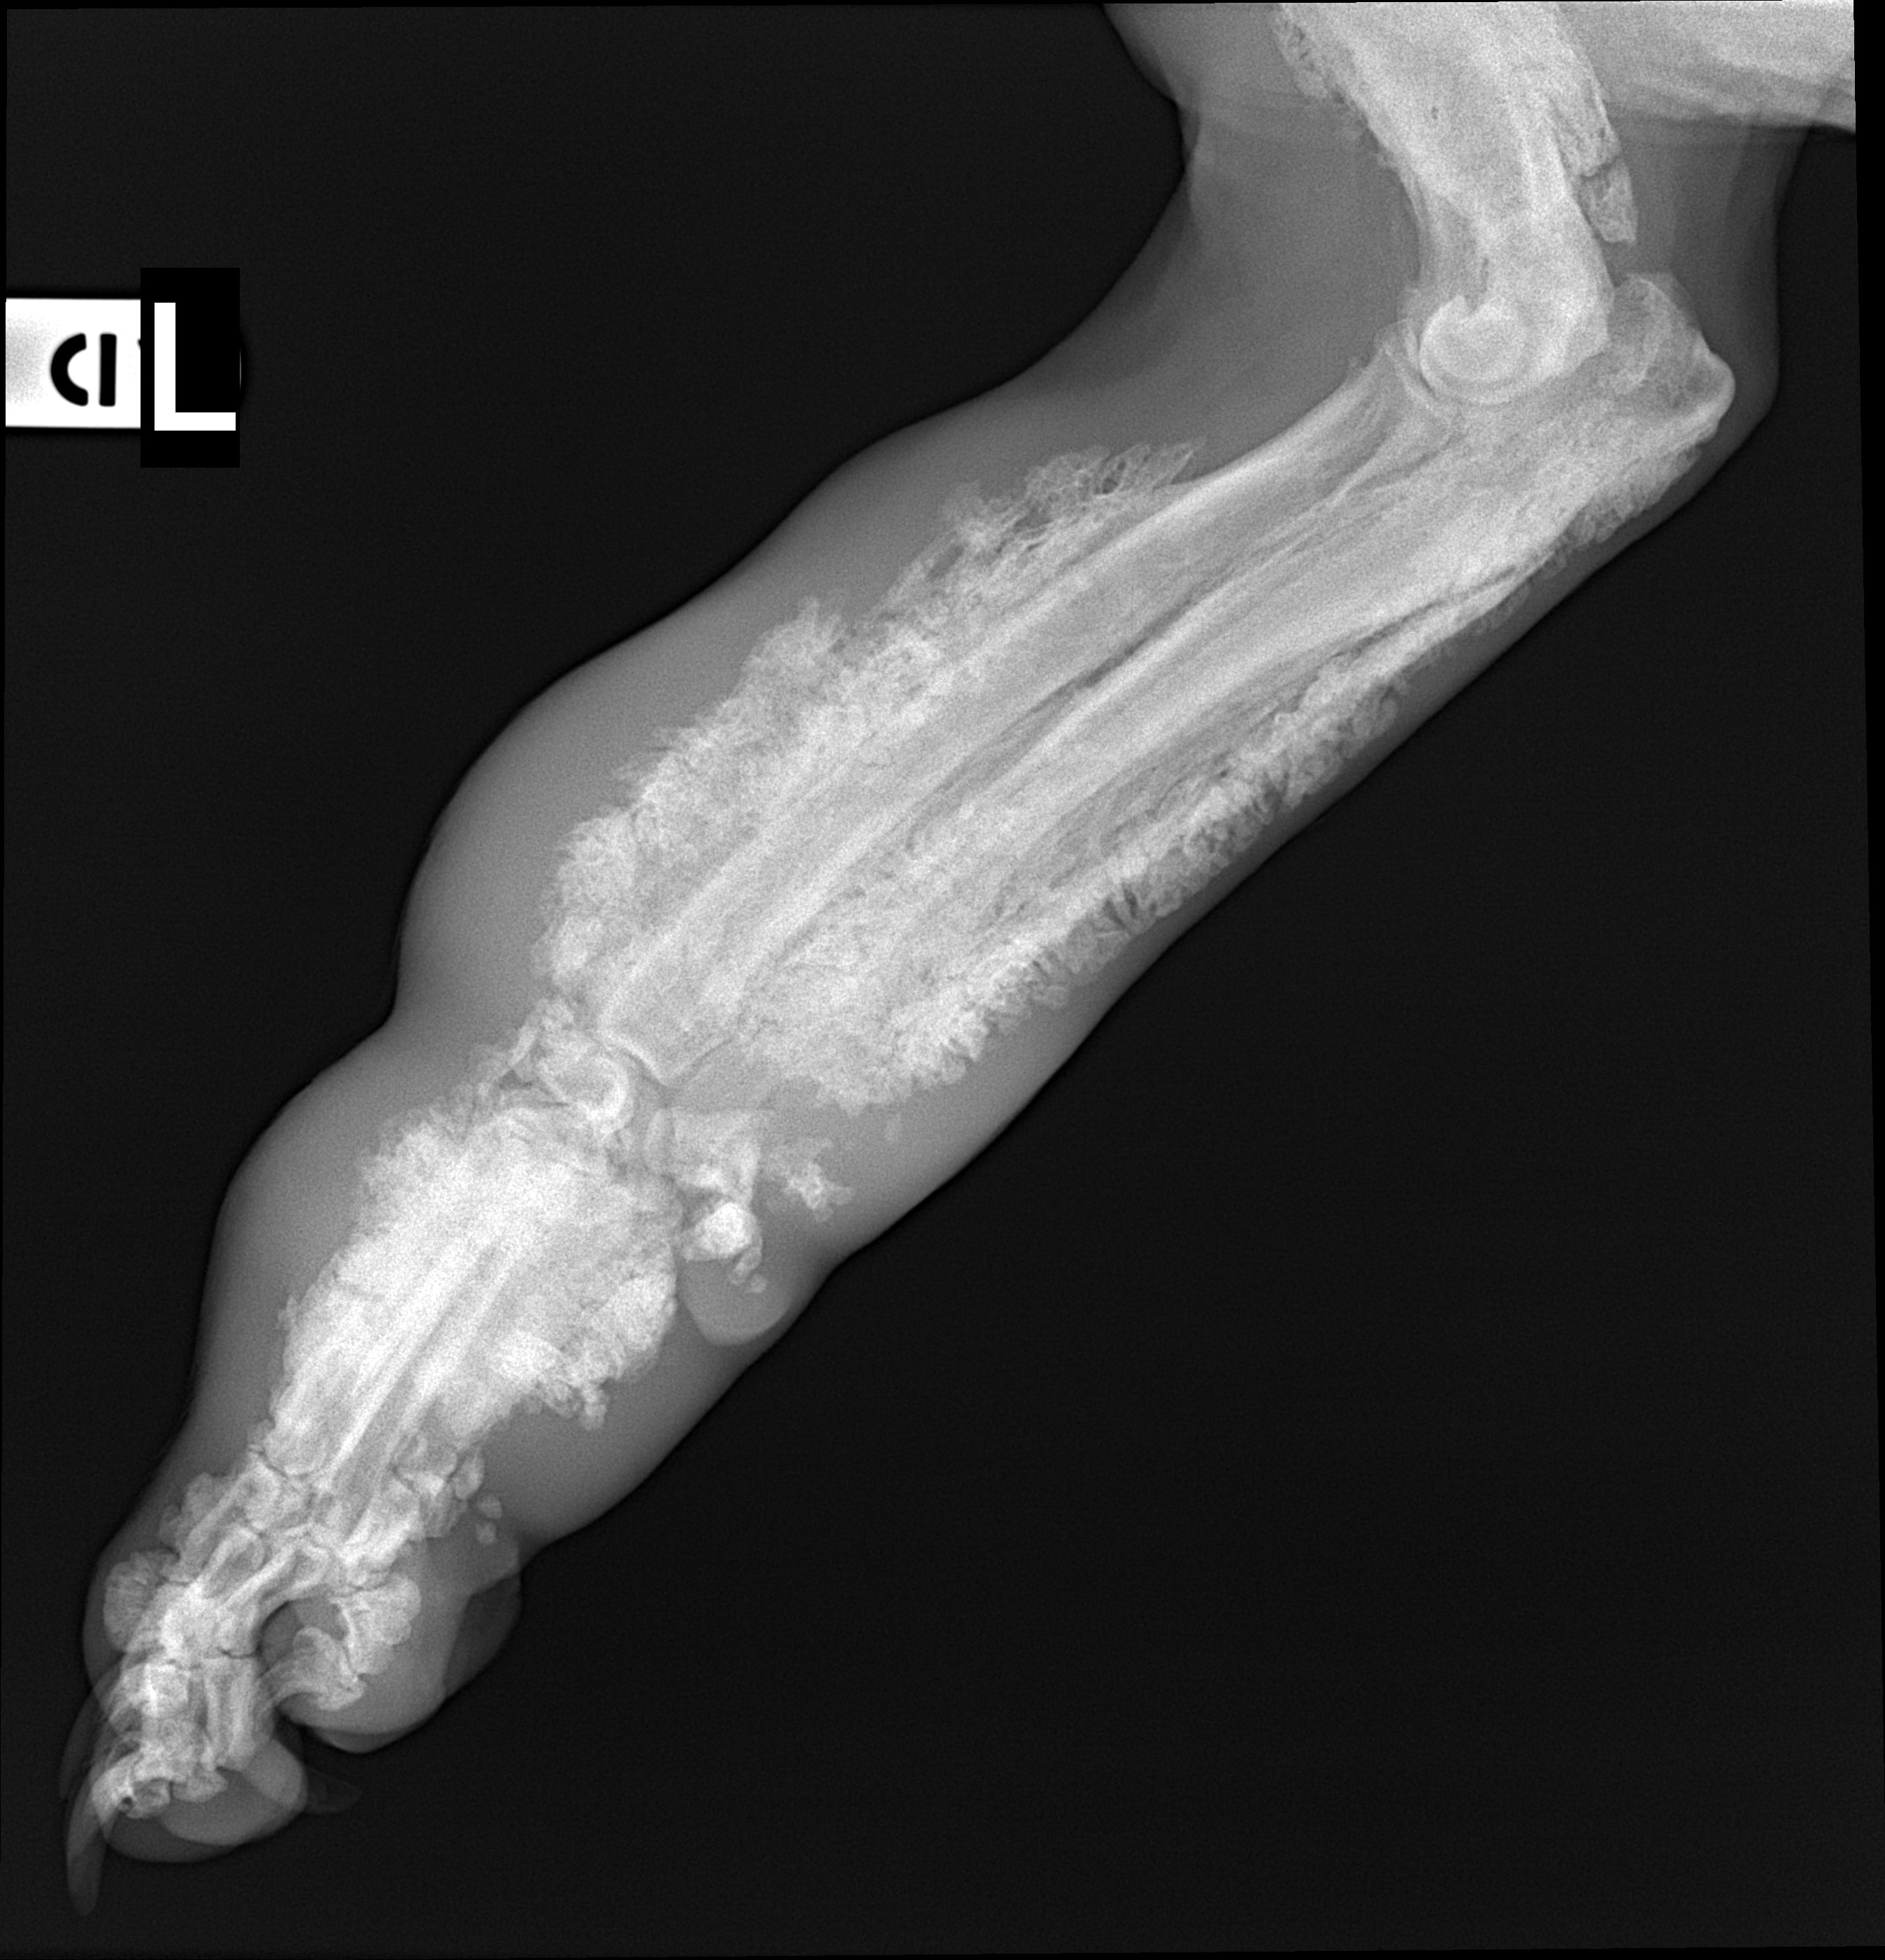

Species: Dog

Specimen: Radiograph

Shown: Hypertrophic osteopathy (Marie's disease) in pulmonary neoplasia